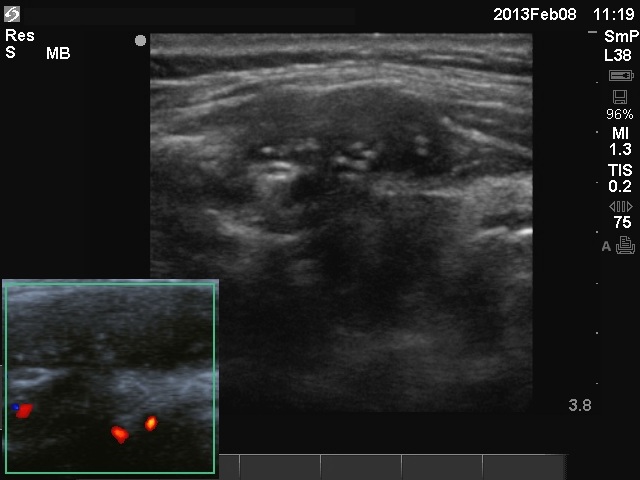

Granulation around surgical thread (cytological diagnosis) - case 1475

There are two granulations both in the left, horizontal and in the right, longitudinal images (arrows). The shape of the masses is irregular. The granulations are hypoechogenic and have one or more echonormal foci.